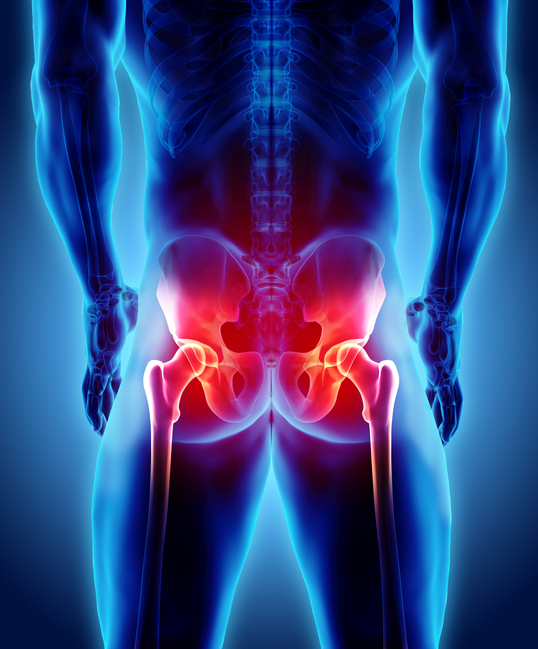

고관절이란?

고관절 통증 증상(엉덩관절)은 오른쪽과 왼쪽의 골반과 넙다리뼈가 연결된 관절의 통증을 일컫습니다. 고관절은 상체의 하중을 분산시키는 역할을 하며, 일어서거나 앉거나 일상생활에서 자주 쓰이는 관절이며 부담도 잘 받게 됩니다. 모양도 크기도 탁구공만 합니다. 일상적으로 걸을 때 고관절에 체중의 3~4.5배의 무게가 실리게 됩니다. 계단을 오를 때는 대퇴골두에 전해지는 무게는 몸무게의 8배, 달리는 경우 10배에 가까운 하중을 견뎌내애 한다고 합니다. 탁구공 크기만 한 대퇴골두가 감당하기에는 너무 무겁기 때문에 고관절이 느끼는 부담도 크고 쉽게 손상될 수 있습니다. 다른 관절과 마찬가지로 감당하기 어려운 충격이나 무게가 가해지면 고관절 통증 증상이 발생하게 되는데요. 퇴행성 고관절염, 대퇴골 골절, 대퇴골두 무혈성 괴사, 선천성 고관절 탈구 등이 대표적인 고관절 통증 질환입니다.